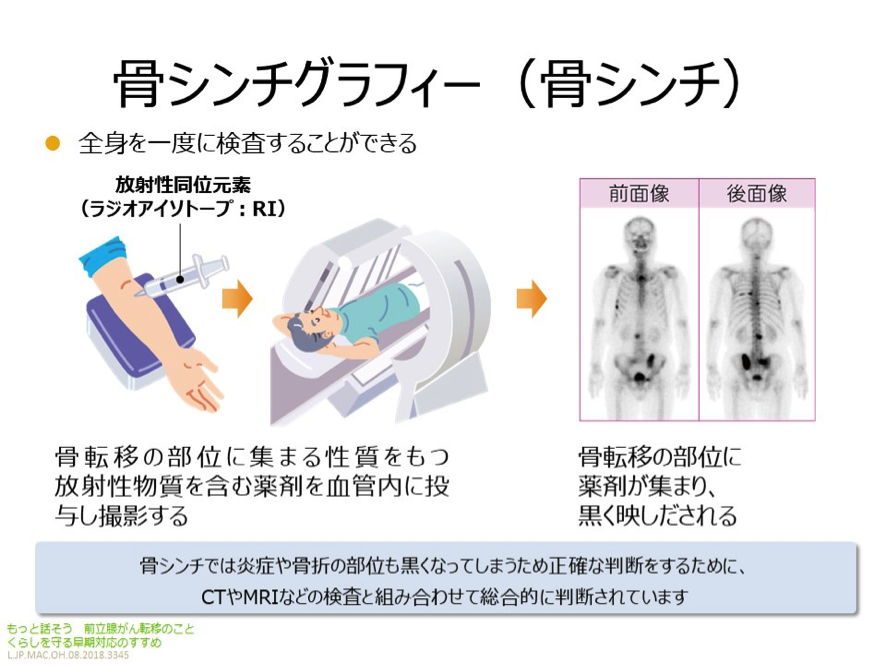

全身骨シンチグラフィ 乳癌 肺癌 前立腺癌等の骨転移病巣の検出

前立腺がんの検査 骨シンチグラフィー 前立腺がんの治療と名医

主な核医学検査 骨 骨シンチグラフィ 核医学検査のご案内 医療関係者

骨シンチグラフィーとは 佐賀大学病院放射線科アンオフィシャル

前立腺がんの検査 画像検査 Ct Mri 骨シンチグラフィ で何がわかる

全身骨シンチグラフィ 乳癌 肺癌 前立腺癌等の骨転移病巣の検出

骨シンチグラフィによる骨転移の診断 Bone Scan Ct Mri画像診断